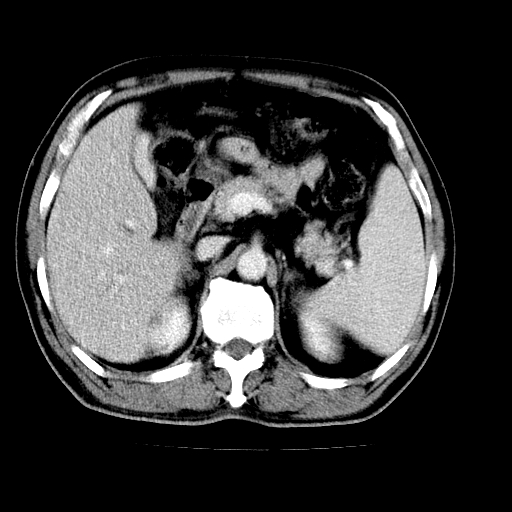

男,66岁,上腹部不适、黄染一周。彩超示:肝左叶占位,肝内胆管扩张,胆总管扩张,胆总管占位?

肝左叶不规则软组织肿块影,边缘不规整邻近肝实质受累分界不清;肝内胆管(左叶)明显扩张成“软藤状”,诊断:肝左叶胆管细胞癌。

肝左叶占位性病变,并胆管扩张,符合胆管细胞癌ct表现,门脉左支受累,左肾囊肿。窗宽太窄了,其他的看不清

左叶胆管细胞癌累及胆总管,门脉左支受侵,慢性胆囊炎胆结石,左肾小囊肿